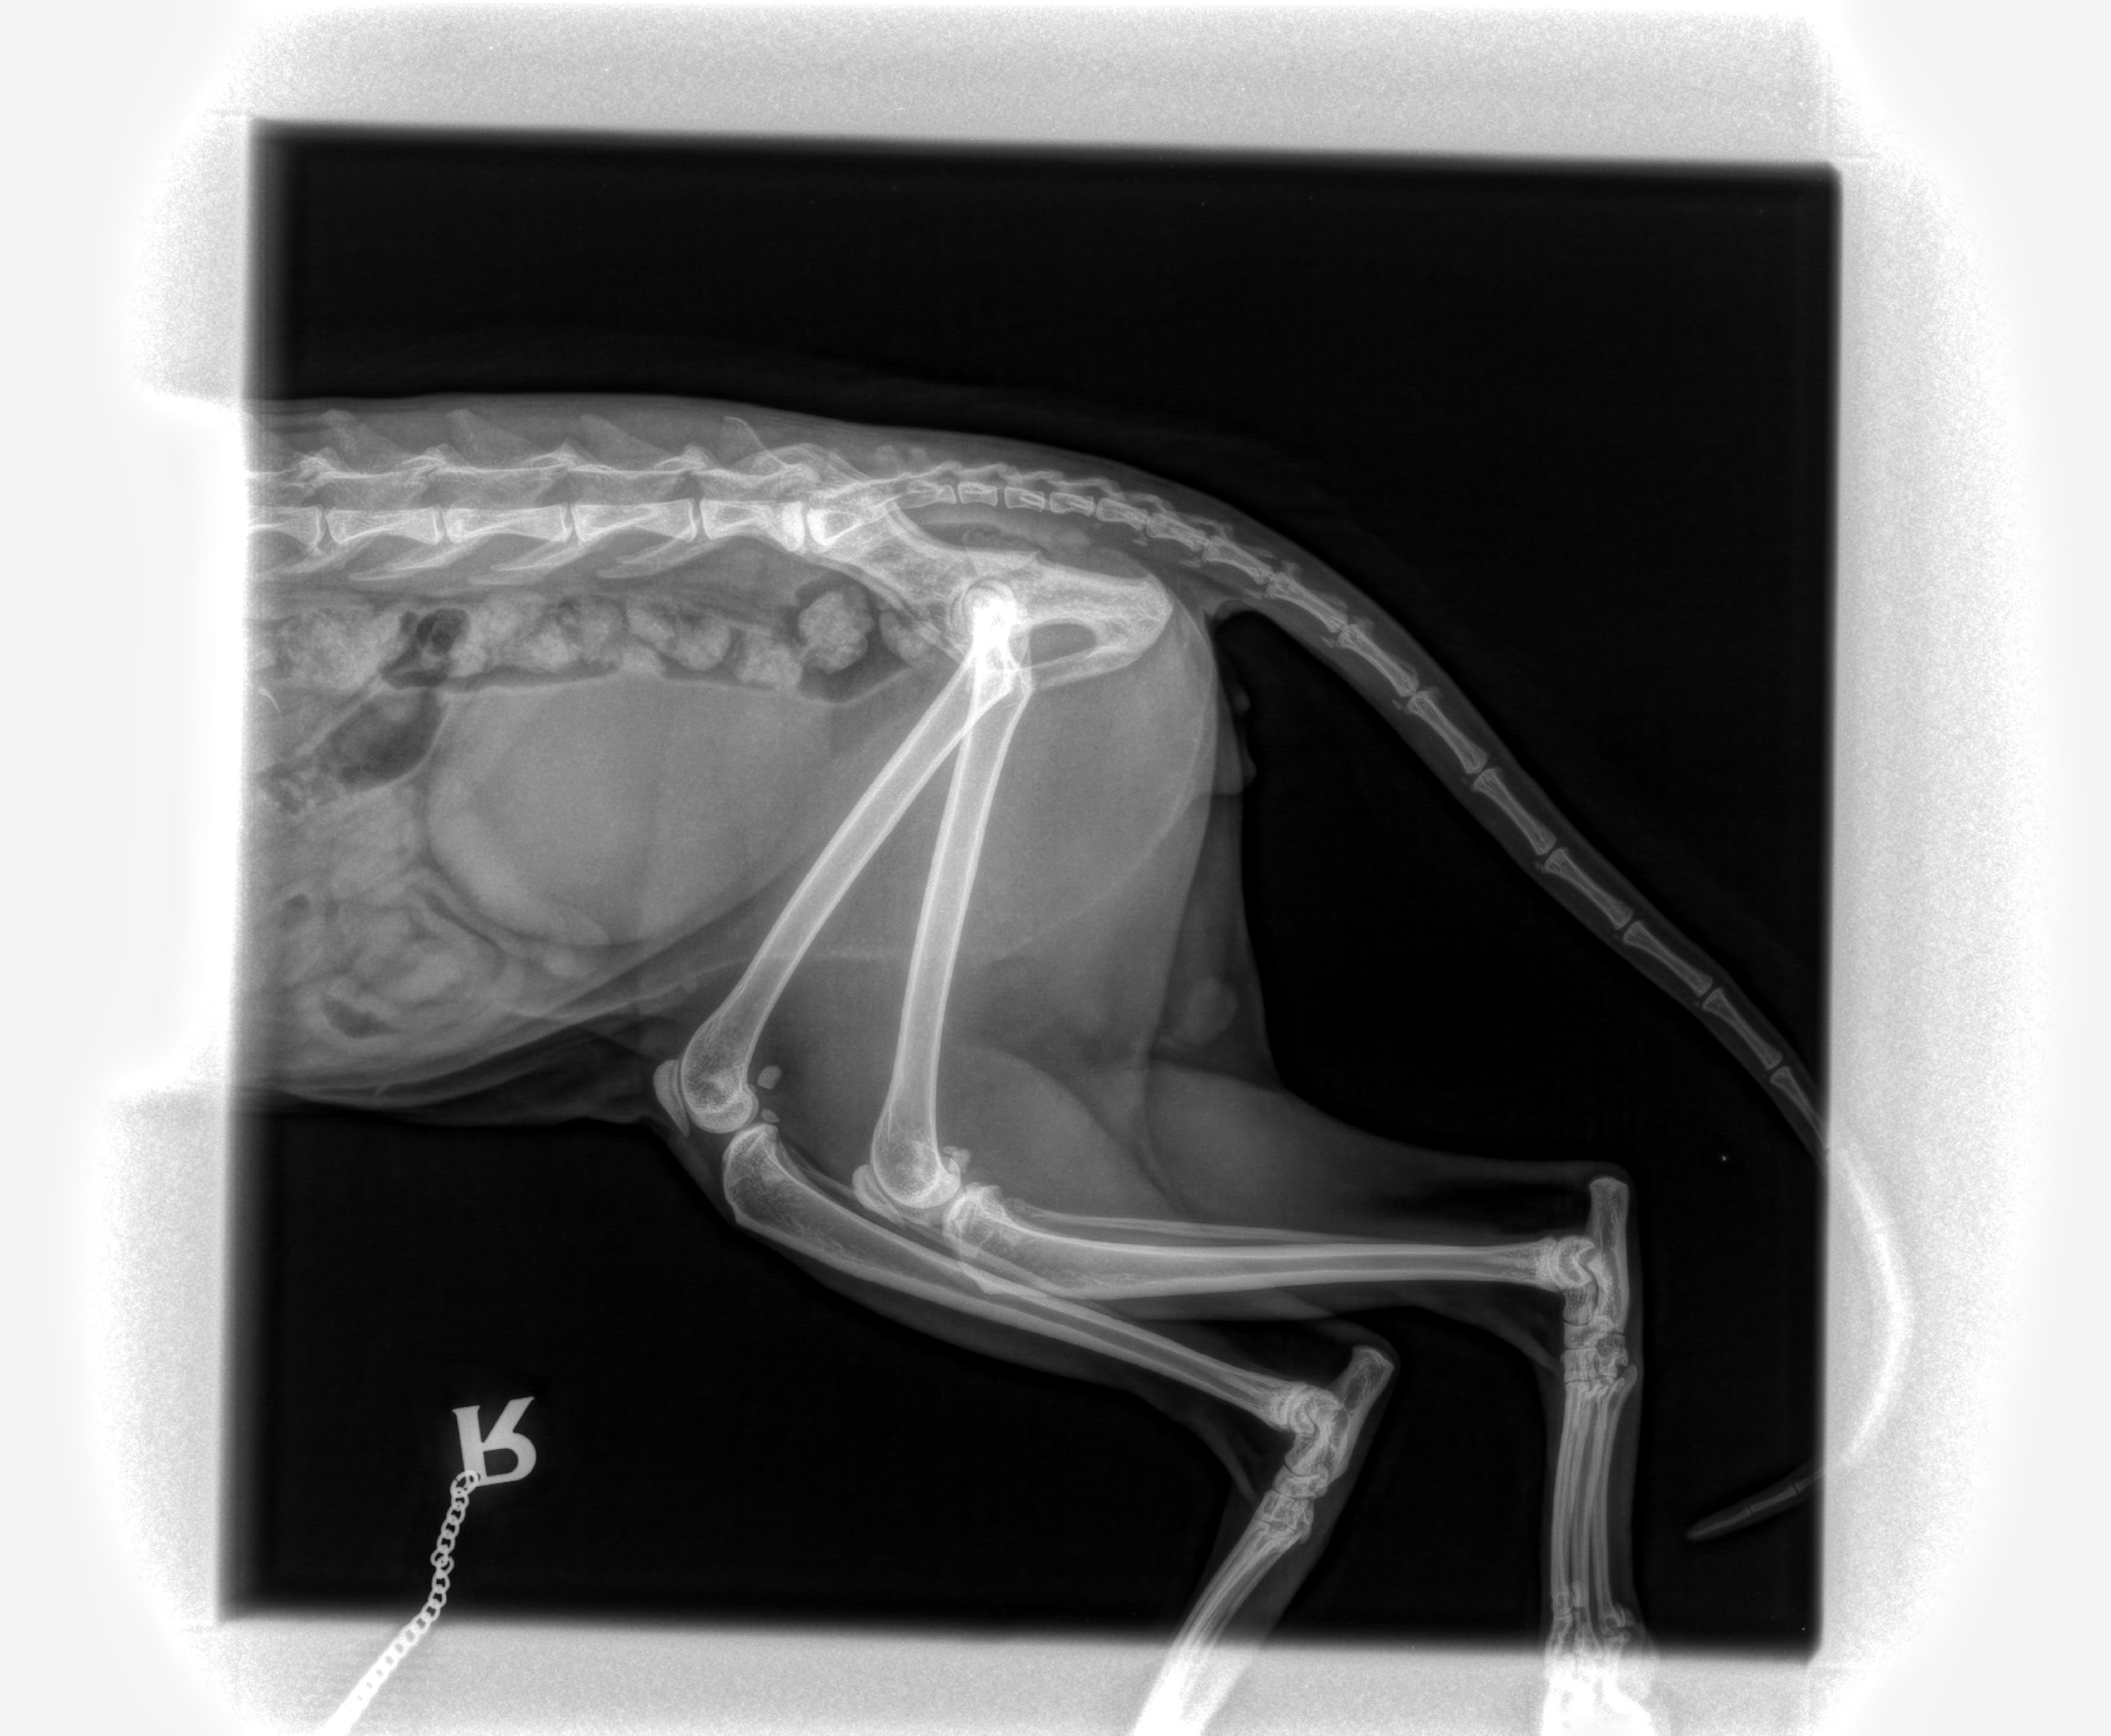

Recently, Twiggy suddenly started hobbling around on just three legs and went off his food. My mum rushed him to the vet, and after initial X-rays, our home vet suspected a severe hip fracture that would require complex surgery.

Crucial Update: Today (30/10/2025), Twiggy was seen by a specialist referral orthopaedic vet. This vet performed new scans and sedation, and they disagree with the initial diagnosis. This means we don't yet have an answer for why Twiggy is in such severe pain.